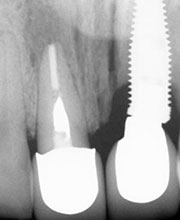

La paciente inconforme con los resultados nos visita, realizamos estudios radiográficos y tomográficos, encontrando que se perdió hueso verticalmente en el implante.

Al término de la distracción dejamos pasar tres meses con una férula en acrílico. En el diente 21 que habíamos visto en la radiografía un problema de un absceso periapical y periodontal.

Radiografía del poste de guía